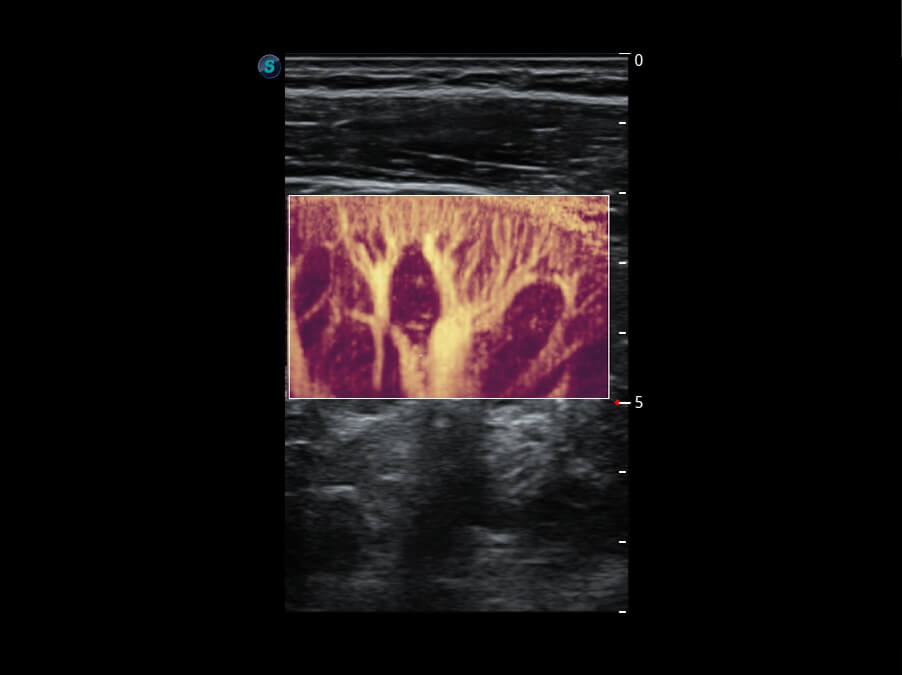

Micro F 显微血流成像 明察秋毫